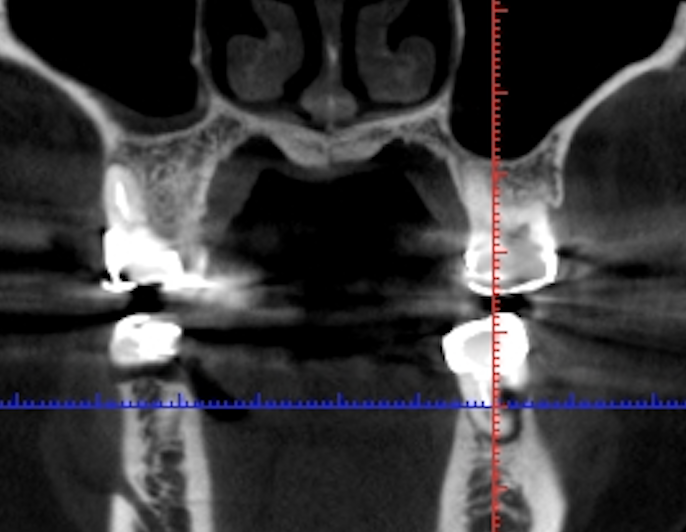

◎歯科用CT画像とレントゲン写真の違いは?

写真は同一部位のレントゲン写真とCT画像です。レントゲン写真は顎骨の形態や走行する神経の位置、歯が生えている方向把握することはできても2次元的な位置関係でしか把握できません。つまり歯や神経の位置がわかっていても実際にどのくらいの位置関係にあるのかを正確に判断することはレントゲン写真では不可能なわけです。しかし、歯科用CT画像では顎骨の形態や走行する神経の位置、歯の生えている方向、さらには骨密度の状態を3次元的に画像化する事が可能なため、より正確な診断する事ができます。